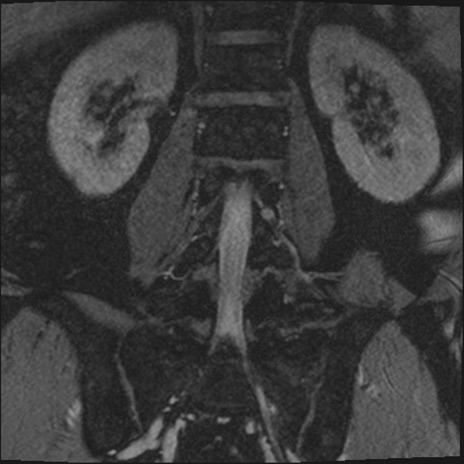

【整形】TIPS症例2 腰椎MRI 3D(冠状断像)

【症例】70歳代男性

【主訴】左下肢痛

【現病歴】2週間前くらいから腰痛、左下肢痛あり。左臀部から大腿、下腿外側のしびれが常時ある。歩行とともに同部位の痛みあり。

【身体所見】Lasegue70-/60+、Bragard-/±、PTR ±/±、ATR -/-、IP 5/5、TA 5/4、TS 5/5、EHL 右第1足趾なし/3、FHL 5/5、hypersthesia(-)、足背動脈触知良好

異常所見と診断は?